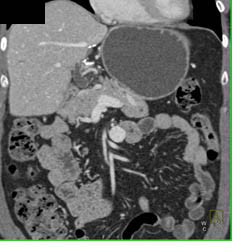

Renal Cell Carcinoma With Liver Metastases